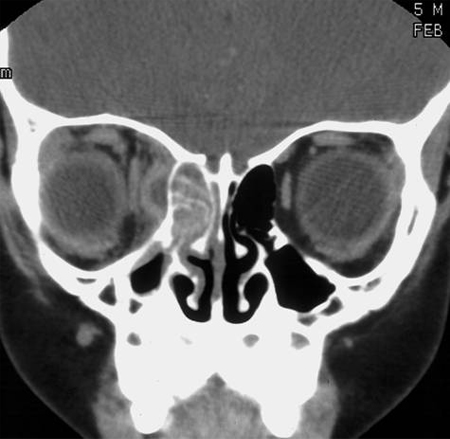

Computed tomography (CT) scan

CT scan with contrast is the imaging study of choice for acute rhinosinusitis with suspected complications.[1]Rosenfeld RM, Piccirillo JF, Chandrasekhar SS, et al. Clinical practice guideline (update): adult sinusitis. Otolaryngol Head Neck Surg. 2015 Apr;152(2 Suppl):S1-39.

However, do not order CT scans for uncomplicated acute rhinosinusitis. This is generally diagnosed clinically and does not require confirmation with imaging.[24]American College of Radiology. ACR appropriateness criteria: sinonasal disease. 2021 [internet publication].

Findings consistent with, but not diagnostic of, acute rhinosinusitis include sinus opacification, air-fluid level, or marked or severe mucosal thickening.[1]Rosenfeld RM, Piccirillo JF, Chandrasekhar SS, et al. Clinical practice guideline (update): adult sinusitis. Otolaryngol Head Neck Surg. 2015 Apr;152(2 Suppl):S1-39.

CT without contrast may be appropriate if invasive fungal rhinosinusitis is suspected or for bony evaluation and surgical planning, but it is not as useful as a contrast CT for detecting orbital and intracranial complications.[24]American College of Radiology. ACR appropriateness criteria: sinonasal disease. 2021 [internet publication].

[Figure caption and citation for the preceding image starts]: Computed tomography scan with right ethmoid sinus opacification and adjacent orbital abscessFrom the collection of Melissa Pynnonen, MD [Citation ends].